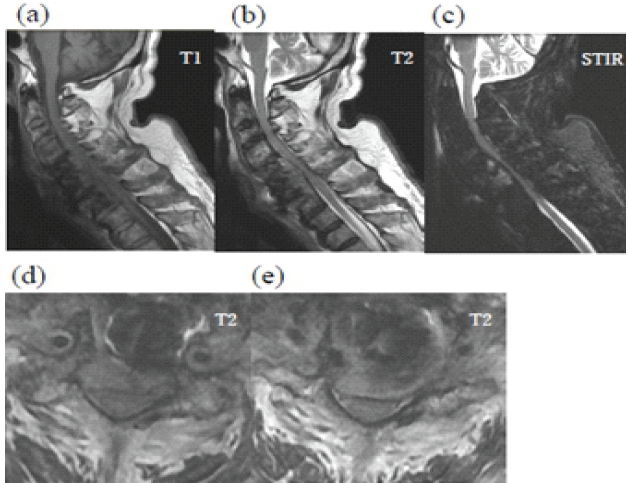

Despite this, his neurological function improved, allowing him to resume independent activities, including recreational baseball. He subsequently stopped attending follow-up visits. At 76 years of age, he returned to the previous hospital with progressive sputum production, worsening limb numbness and weakness, and gait disturbance. Physiological and neurological evaluation revealed bilateral lower-extremity weakness (manual muscle testing: digit extensor 4/4, iliopsoas muscle 3/2, quadriceps muscle 4/4, tibia anterior muscle 5/3, and extensor hallucis longus muscle 4/2), heightened patellar and Achilles tendon reflexes, and dysphagia. His cervical Japanese Orthopaedic Association (JOA) score was 6.5. Radiographs and computed tomography demonstrated vertebral osteolysis around the implant, absence of the right C6 screw, and air between the anterior implant surface and the esophagus (Fig. 2). Magnetic resonance imaging revealed a high-signal lesion from C5 to C7 on short tau inversion recovery sequences with spinal cord compression (Fig. 3). Upper gastrointestinal endoscopy revealed a 2-cm esophageal mucosal perforation with direct exposure of the cervical implant (Fig. 4).

Figure 2: Magnetic resonance imaging of delayed esophageal perforation. Sagittal T1-weighted (a), T2-weighted (b), and short tau inversion recovery (c) images are shown in the upper row. Axial T2-weighted images at the C5/6 (d) and C6/7 levels (e) are shown in the lower row. Signal changes are observed in the C4-C6 vertebrae, and the spinal cord is compressed from the anterior aspect.